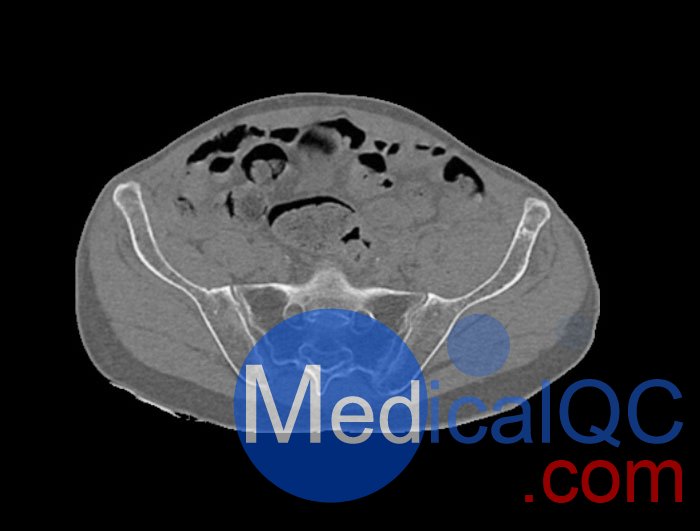

左側(cè)股骨頸移位骨折。

WEK54-01股骨頸骨折骨盆模型,WEK54-01骨盆模體提供了對(duì)軟組織和骨組織的詳細(xì)而逼真的模擬??障吨刑畛渲s-160HU的纖維素-聚合物復(fù)合材料。

骨骼和軟組織的逼真模擬。